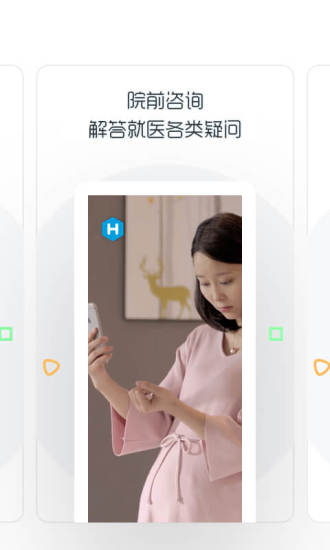

1.院前咨询服务

和缓平台提供院前咨询服务,在去医院就诊之前,医生会指导用户找到合适的科室及医院,帮助用户了解就医流程、解答疑问给出建议,省去了上网搜索查询的繁琐过程、高效快捷。